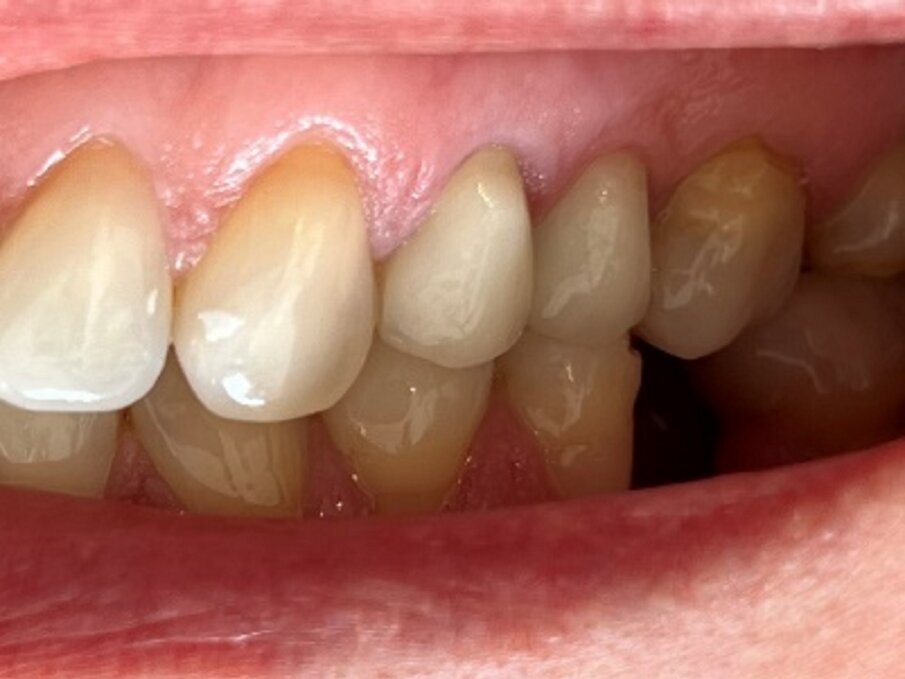

Dopo la prova, il restauro finale è stato cementato in bocca utilizzando vetroionomero, Fuji One (GC). Le immagini finali mostrano un follow up postoperatorio della situazione clinica a due e dieci mesi e una gengiva perfetta (Figg. 6 e 7).

Fig: 7: Controllo dopo dieci mesi.